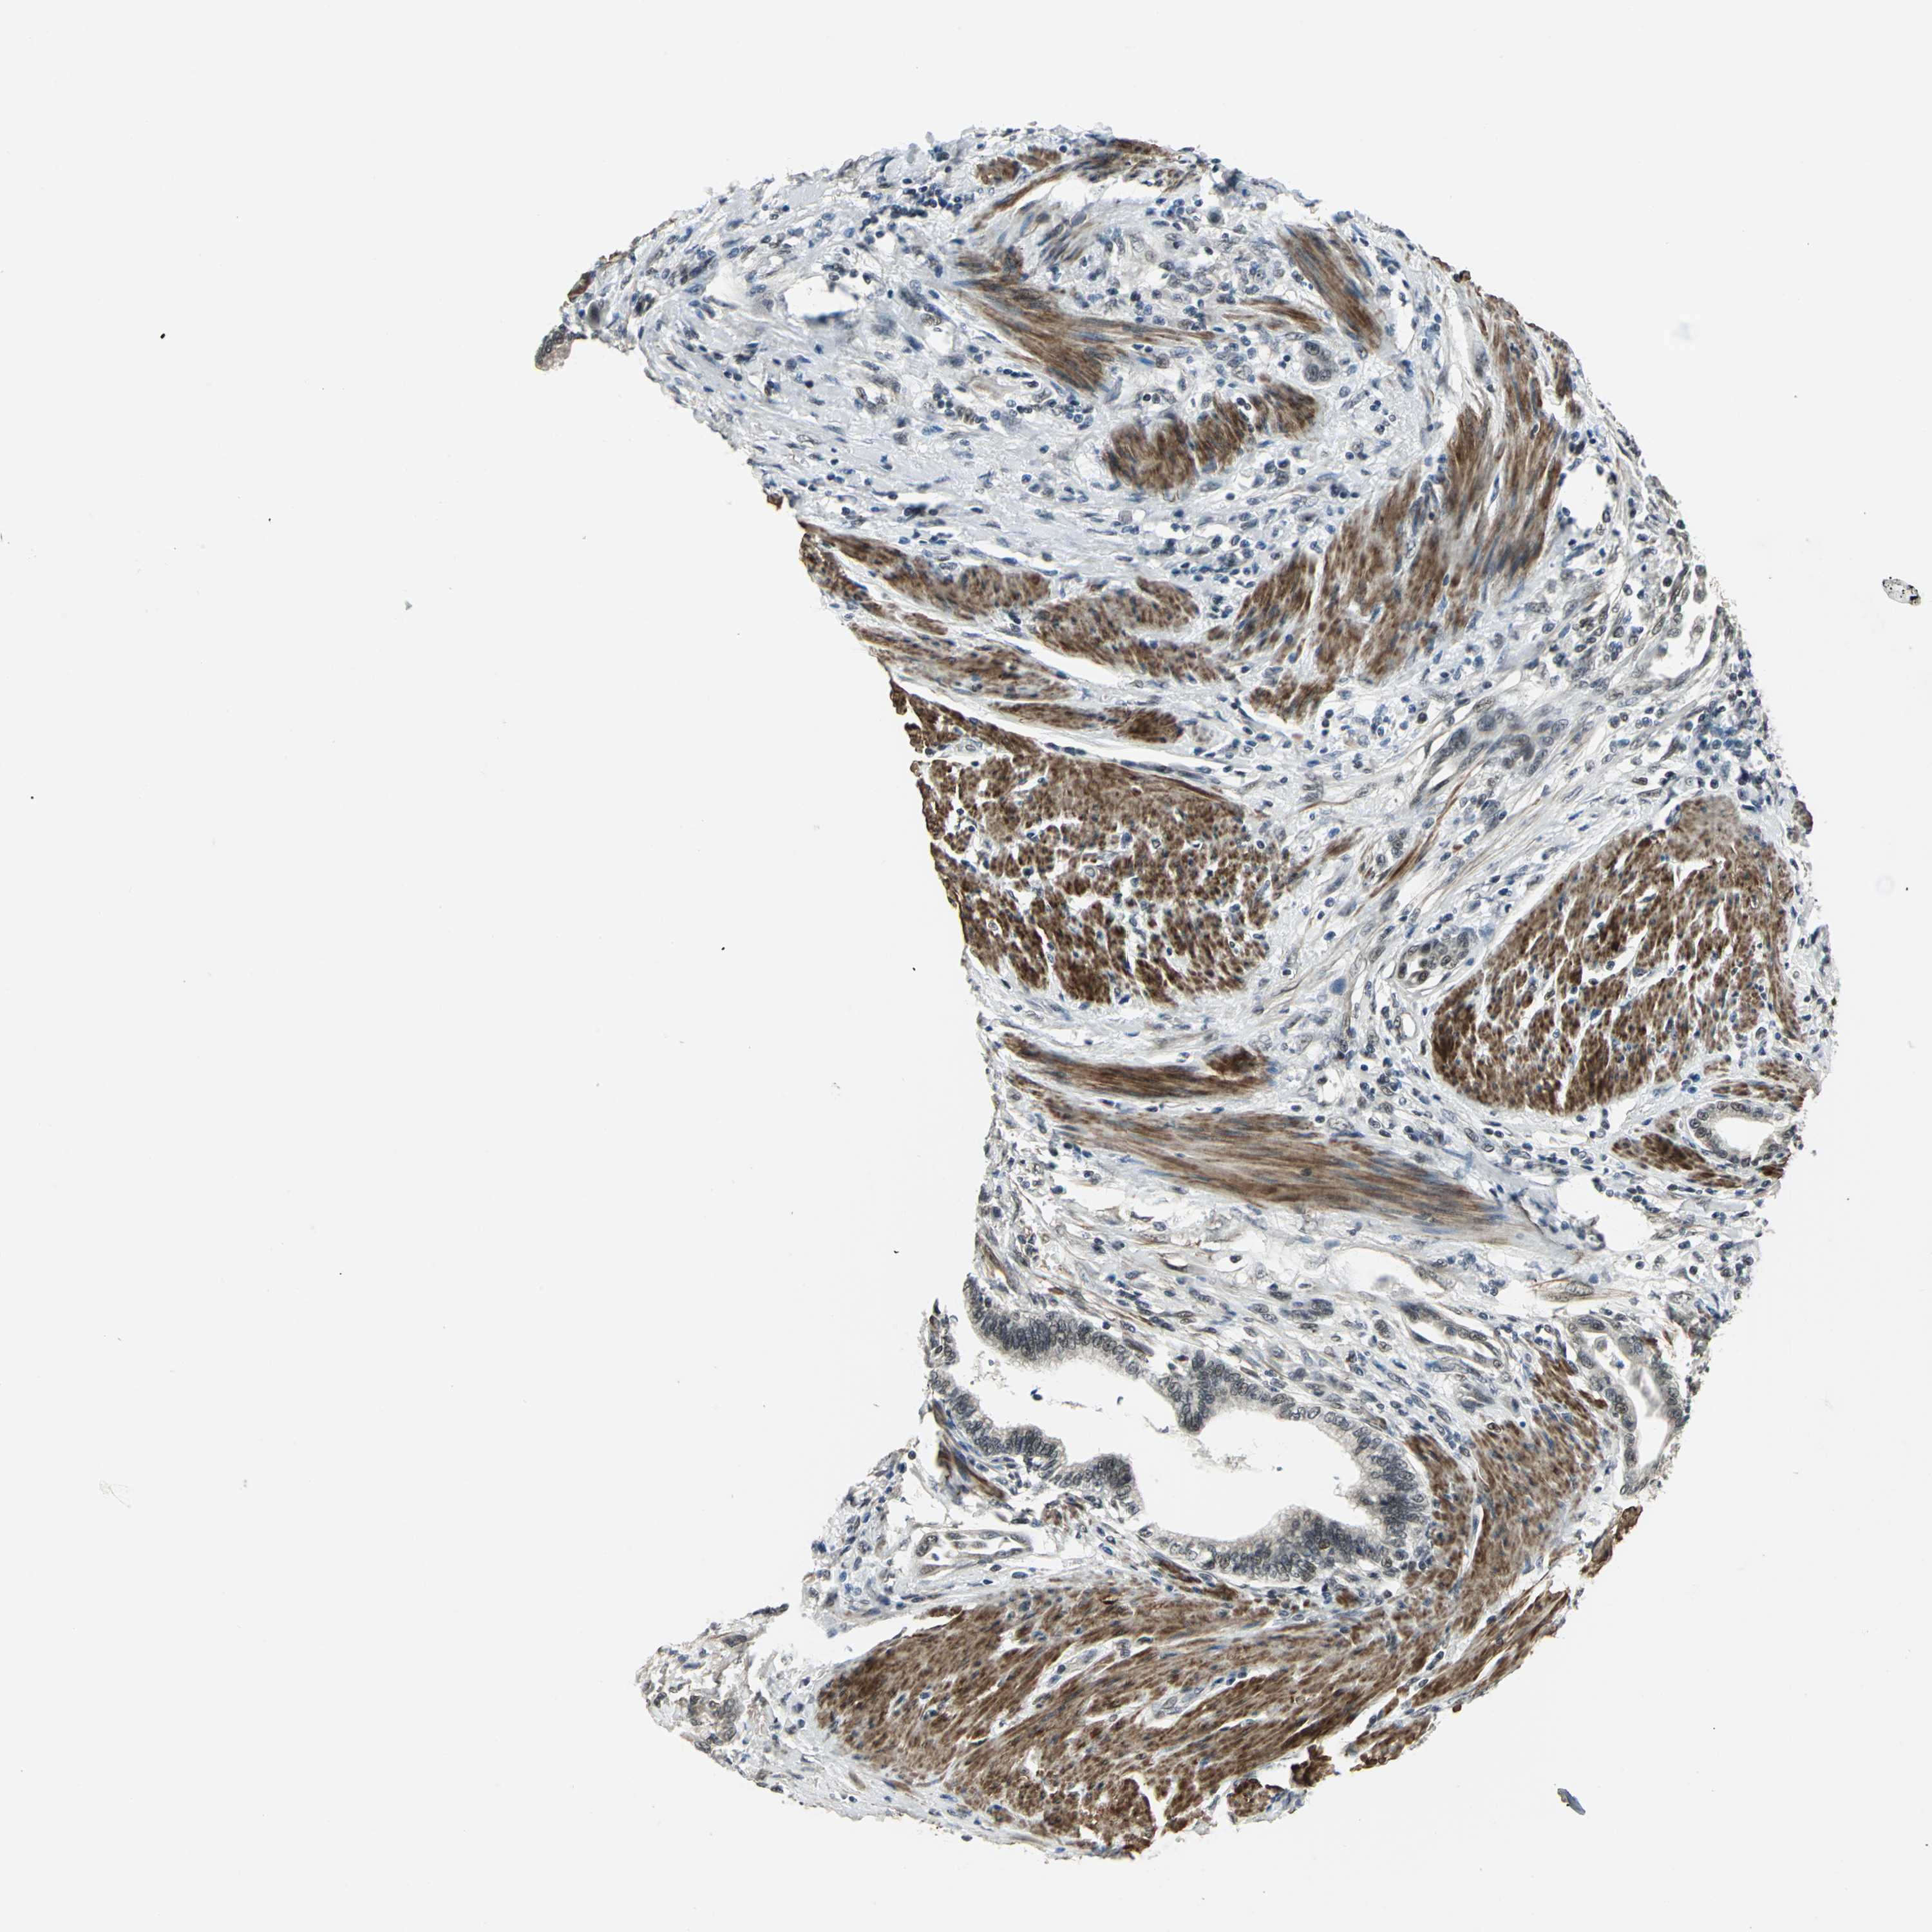

PANCREATIC CANCER - Protein expressioni

A mouse-over function shows sample information and annotation data. Click on an image to view it in a full screen mode. Samples can be filtered based on level of antibody staining by selecting one or several of the following categories: high, medium, low and not detected. The assay and annotation is described here.

Note that samples used for immunohistochemistry by the Human Protein Atlas do not correspond to samples in the TCGA dataset.

Antibody stainingi

Antibody staining in the annotated cell types in the current human tissue is reported as not detected, low, medium, or high, based on conventional immunohistochemistry profiling in selected tissues. This score is based on the combination of the staining intensity and fraction of stained cells.

Each image is clickable and will lead to virtual microscopy that enables deeper exploration of all samples and also displays staining intensity scores, fraction scores and subcellular localization as well as patient and tissue information for each sample.

Antibody HPA005544

Antibody CAB004508

Staining

High

Medium

Low

Not detected

Intensity

Strong

Moderate

Weak

Negative

Quantity

>75%

75%-25%

<25%

None

Location

Nuclear

Cytoplasmic/membranous

Cytoplasmic/membranous,nuclear

Adenocarcinoma, NOS